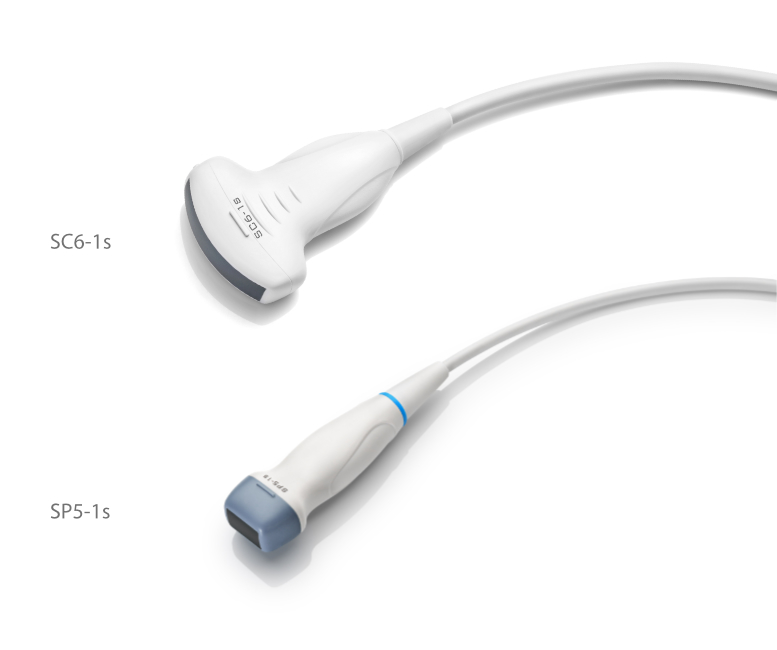

Transducers